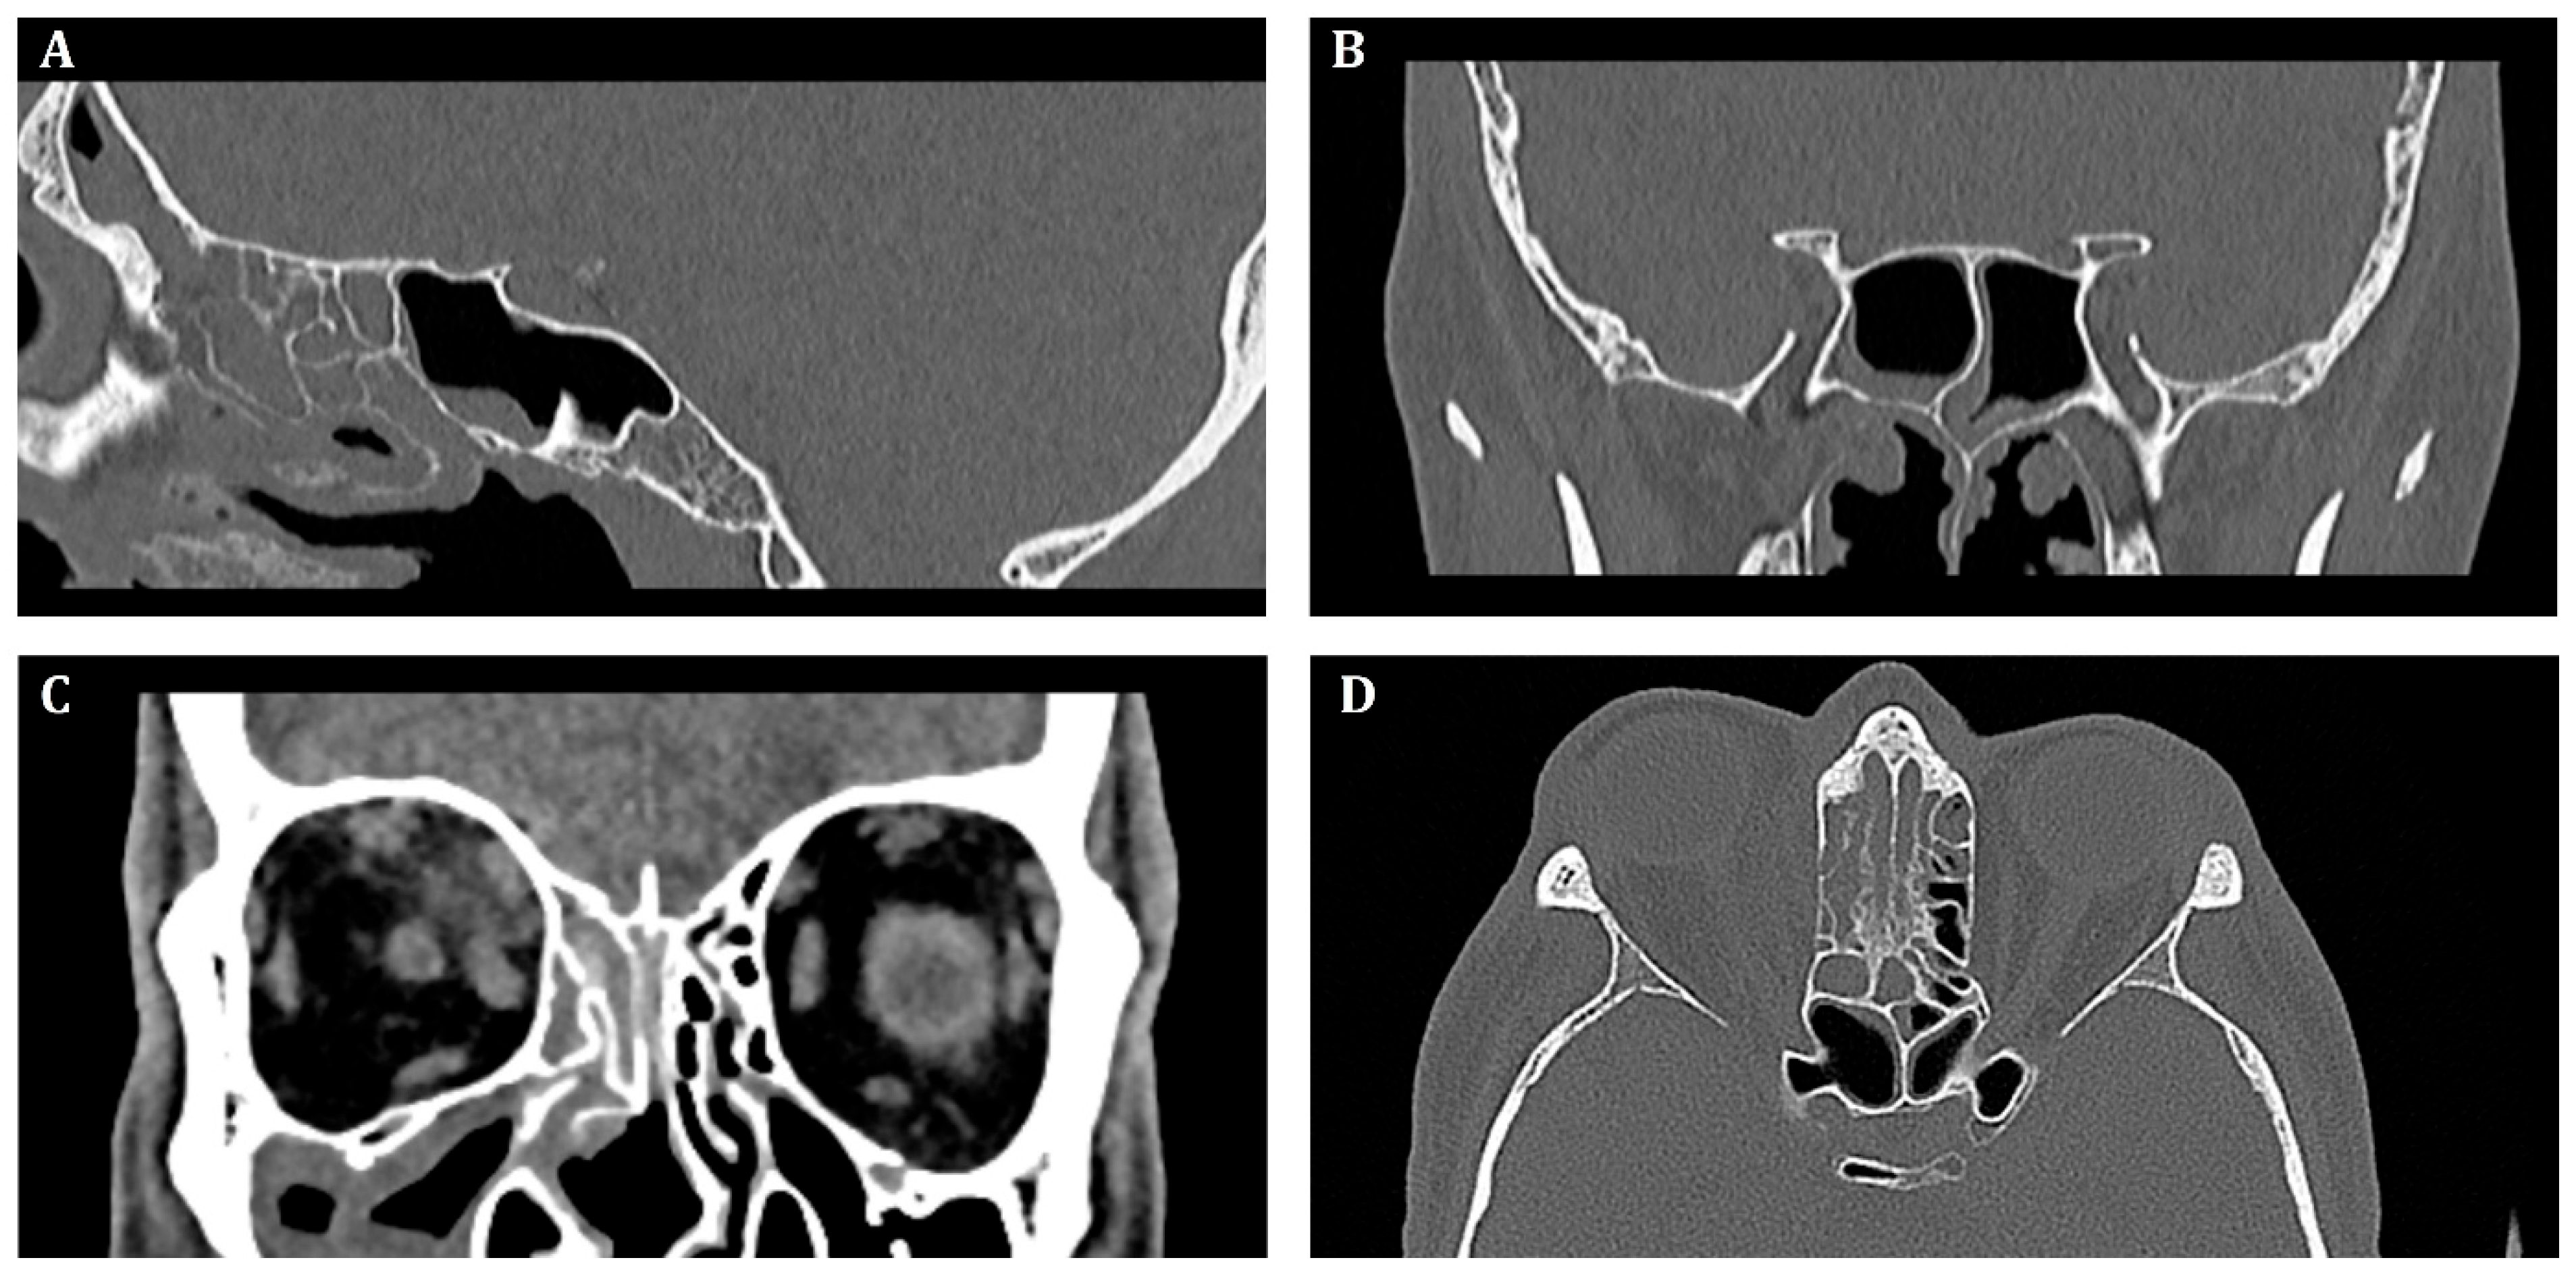

Initial, pre-operative CT scans with massive inflammatory opacifications are presented in Figure 2.

Figure 2. Pre-operative computed tomography of the sinuses, (A)—sagittal, (B,C)—frontal, (D)—transverse scan. Inflammatory opacification in frontal, maxillary and ethmoid sinus on the right side. Suspected abscess in the upper-medial quadrant of the right orbit.